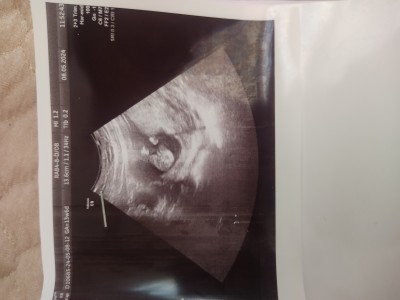

merhaba anneler:kissing: 12 haftada kıza benzetmişdi, 14 de erkek dedi. Ama yine emin konuşmadı istersen 1 hafta sonra gel yine bakalım dedi. İşlerden dolayı gidemedim. Üstden göstermemişti,altdan muayeneyle baktı. Bacak arası böyle resim verdi. Sizce çıkıntı organmı yoksa göbek bağı mı?

Gebelik haftası 15

Valla canım bence erkek gibi çıkıntısı var

Bana göbek bağı gibi geldi

Evet göbek bağı.buyuk ihtimalle kız